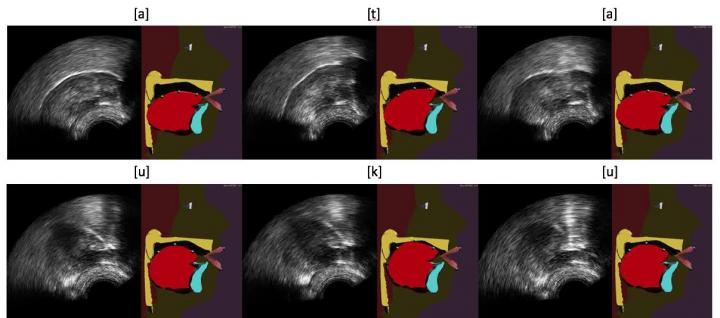

image: This is an example of tongue model animations of the GIPSA-Lab articulatory talking head from ultrasound images, using the Integrated Cascaded Gaussian Mixture Regression algorithm for [ata] (top) and [uku] (bottom) sequences. view more

Credit: Thomas Hueber / GIPSA-Lab (CNRS/Université Grenoble Alpes / Grenoble INP).